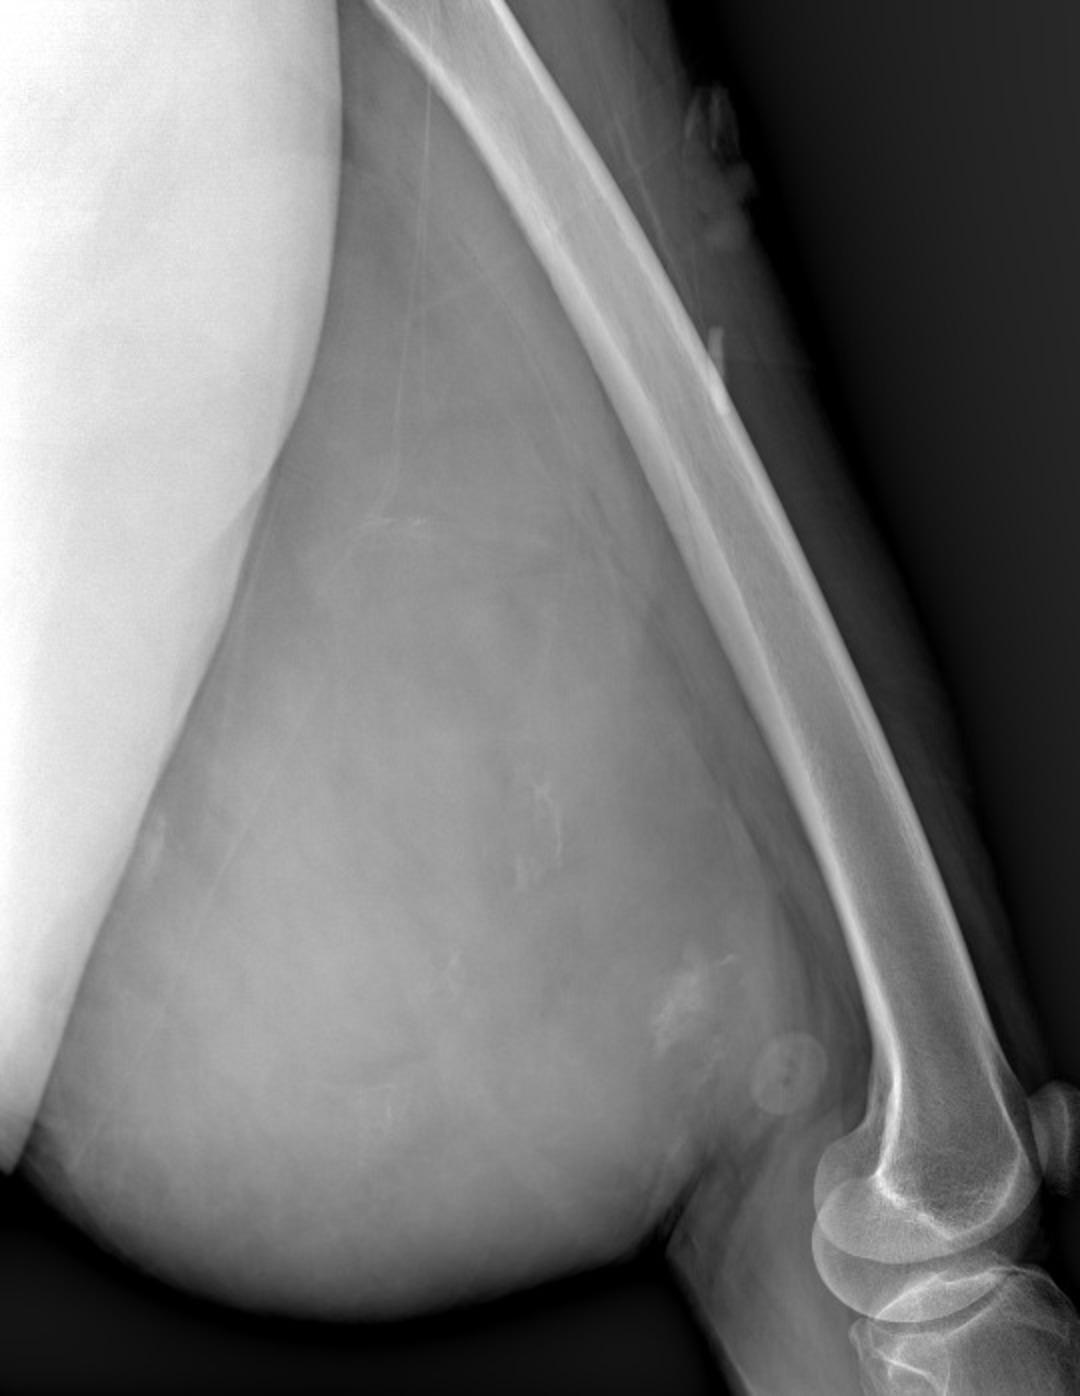

Muayenede yumuşak doku kitlesi olduğu değerlendirilen şişliğin alınması için Ortopedi ve Travmatoloji Anabilim Dalı Öğretim Üyesi Prof. Dr. Emin Özkul ve ekibi tarafından ameliyat kararı verildi. Yaklaşık 2 saat süren operasyonla kitlenin çıkarıldığı, kitlenin 5 kilo 668 gram geldiği belirtildi.

Prof. Dr. Emin Özkul, vücutta görülen kitlelere büyümeden müdahale edilmesi gerektiğini ifade ederek, “Hastamız 42 yaşında bir kadın. Komşu şehir Mardin’den geldi. Bölge hastanesi olduğumuz için bu tür hastalar Mardin’den, Şırnak’tan ve diğer illerden çok geliyor. Bu hastalara önerimiz; ‘küçük bir kitle, ağrısız bir kitlem var, ele gelen bir şişliğim var ama bunda ağrı olmadığı için herhangi bir şey olmaz’ dememeli. En yakın sağlık kuruluşuna başvurup en azından kitlenin bir öneminin olup olmadığını teyit edilmesi, bir uzman tarafından bunun doğrulanmasını istiyoruz. Bu hasta da 3 yıl önce fark edilmiş küçük bir kitle, zamanla çok büyük boyutlara, yaklaşık 6 kiloya varan boyutlara varmıştı. Neredeyse bütün bacak boyu yayılan bir kitlesi mevcuttu. Bu kadar büyümenin şöyle sıkıntıları oluyor, kişinin bacağında, kolunda fonksiyon kaybına, yeri geliyor ekstremite kaybına, yani bacağını kaybetmesine yol açabilecek sıkıntılara yol açıyor. Küçükken bunlarla baş etmek daha kolay. Kişinin ekstremitesinde, bacağında, kolunda bir sıkıntı yaratmadan bunları telafi etmek, bunları alıp çıkartmak, ameliyatla bunları tedavi etmek daha kolayken bu boyutlara vardığında kişinin bacağında, kolunda fonksiyon kaybı, sakatlık riski çok yüksek oluyor. Bu sebeple küçükken önleminin alınmasında yarar var” dedi.

Kitlelerin görülmesi halinde sağlık kuruluşlarına başvurulması gerektiğini belirten Prof. Dr. Özkul, “Hastamızda yaklaşık olarak 3 yıl önce şikayetleri başlamış. Sonra zaman içerisinde hızla büyüyen bir kitleye sahipti. Şanslıydı ki herhangi bir sinirine zarar vermemişti. Hayatına fonksiyon bozukluğu olmadan devam edebilecek. Bölgemize yaşayan ve ülkemizde yaşayan herkese şunu söylüyoruz. Küçük de olsa yumuşak doku kitlelerini önemsemeleri ve uzman görüşü almalarını öneriyorum. Bu hastadan 5 kilo 668 gramlık bir kitle çıkarttık. Bu benim mesleki yaşamım boyunca çıkarttığım en büyük kitlelerden bir tanesiydi. Biraz daha büyük boyutlara varmış olsa kişinin bacağını kurtarma şansınız olmuyor. Bu sebeple bunlara dikkat etmek gerekiyor. Hızlı büyüyen bir kitleniz var ise, ağrısız da olsa mutlaka ve mutlaka tedavi için en yakın sağlık kuruluşuna veya bizim üniversitemizin polikliniklerine başvurabilirsiniz” diye konuştu.